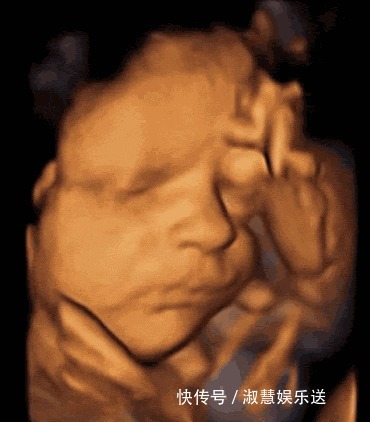

五、含指头每个细心的妈妈都会发现,宝宝出生后很喜欢吃手指,没事就会含着指头呵呵笑,其实这是种本能,宝宝在肚子里时也会有这些举动,这种举动可以很好的为母亲哺乳婴儿打好基础。

文章插图